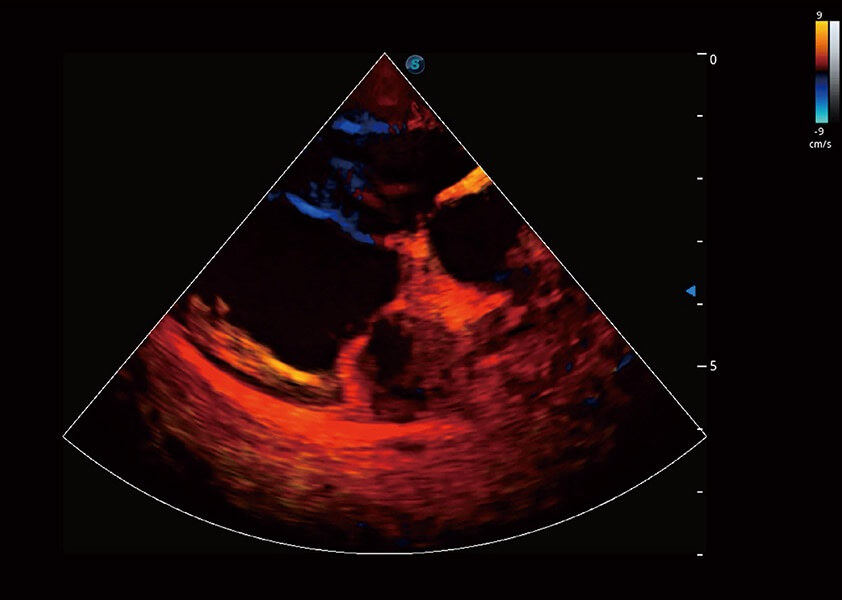

ProPet 60 作為一款高端臺式動物超聲設備,為動物醫(yī)生的日常診斷提供了一系列貼合動物臨床需求、解決臨床實際問題的高級成像功能。憑借全系列高清探頭,滿足醫(yī)生對腹部、心臟、生殖、淺表、肌骨等成像的所有需求,切實幫助您提升檢查效率,提高診斷信心。